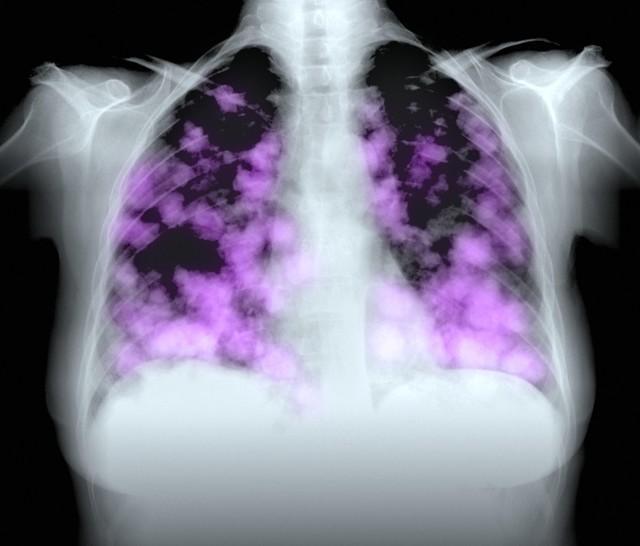

根據數據顯示,2020年,共有300萬人死於癌症,其中71萬人死於肺癌,遠遠超過其他癌症。在生活中,大多數人都知道肺癌通常是由各種細胞的異常生長引起的。另一方面,肺癌主要是由支氣管粘膜中的異常細胞引起的,而這些異常細胞的出現,就可能會導致各種症狀的發生,如咳血。這不僅降低了我們的生活質量,而且還增加了世界人口的死亡率。

那麼,爲什麼我國的肺癌患者變得越來越多了呢?坦率地說:除了吸菸,還有5個主要原因。但生活中有許多人認爲,只要自己不吸菸,肺癌就不會找上自己,但很多人不知道的是,世界上15%的肺癌其實發生在非吸菸者身上。